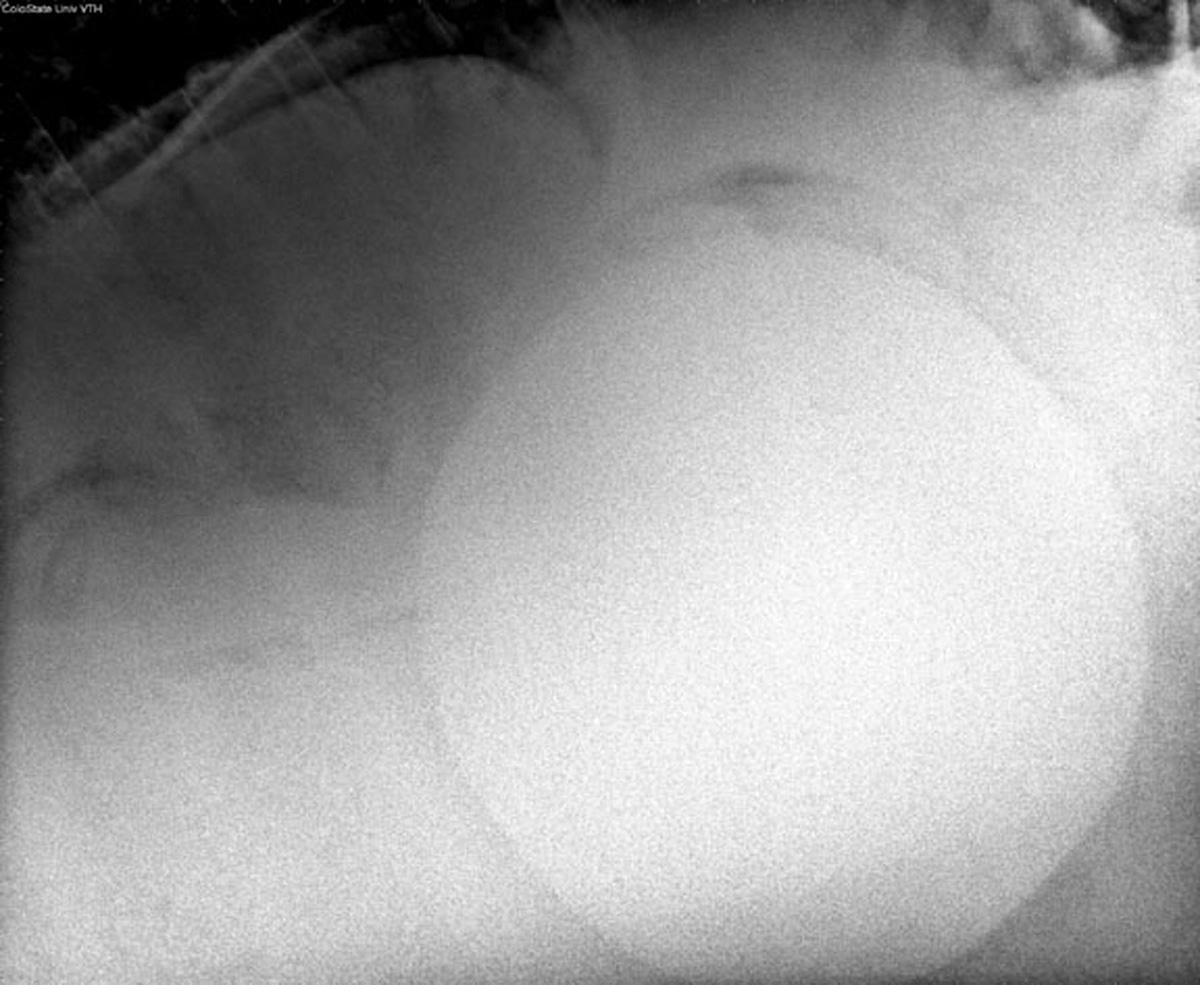

Any time a horse passes a small enterolith, Hassel strongly recommends making an appointment at a veterinary referral facility to have abdominal radiographs performed.

“If there are no large enteroliths present (all are smaller), it may be possible to manage these cases long-term without surgery,” says Hassel. “If larger enteroliths are present, surgical management on an elective basis is a lot less risky and less expensive than an emergency colic surgery.”

When abdominal radiographs reveal the presence of an enterolith too large to pass through the GI tract, surgery is the only solution.